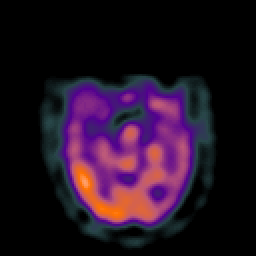

Subacute Stroke overlay -- Slice #8

[Home][Help][Clinical] Slice 8